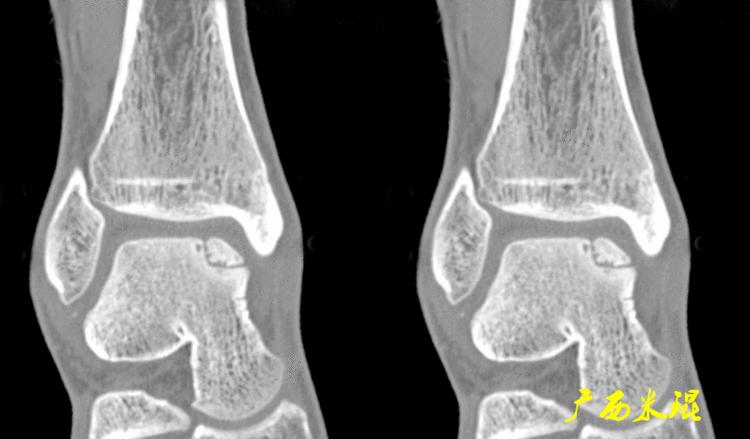

(2)CT检查

CT检查相对于X线检查而言更细致,但没有MR敏感,如果仅仅是软骨的病损,CT也容易漏诊。

即使这样,CT检查能够进行三维成像,可以更加直观的显示软骨剥脱的具体情况,这可是其他检查无法实现的。